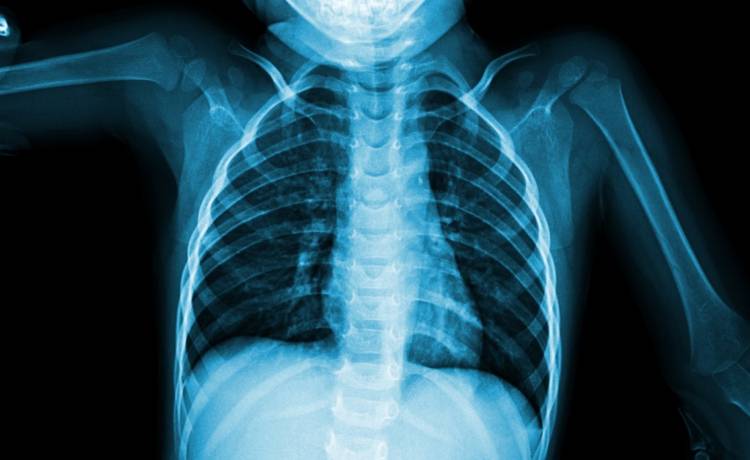

Gdy dotarli do placówki leczniczej, niemowlę było w ciężkim stanie. Jak informuje brytyjski portal The Mirror, lekarze natychmiast rozpoczęli przeprowadzanie niezbędnych badań. Jednym z nich było zdjęcie rentgenowskie klatki piersiowej dziecka. To, co specjaliści zobaczyli na kliszy, bardzo ich zdziwiło i przeraziło. Ze zdumieniem odkryli, że w serce dziewczynki wbiła się czterocentymetrowa igła do haftowania.

Według komunikatu wydanego przez rzecznika Szpitala Dziecięcego Xi'an w prowincji Shaanxi w Chinach igła przeszła przez ścianę żołądka dziecka i przebiła lewą komorę serca. Lekarze zadecydowali o pilnej operacji. Dzięki chirurgicznej interwencji udało się sprawnie usunąć niebezpieczne ciało obce z organizmu niemowlęcia. Jak informują brytyjskie media, dziewczynkę zabrano na oddział intensywnej terapii w celu monitorowania i dalszego leczenia.